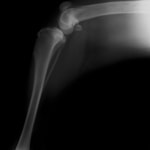

症例1:グレート・ピレニーズ、11歳齢、避妊メス

慢性的な右前肢跛行、右肩関節伸展時の顕著な疼痛身体検査において、棘上筋、棘下筋および上腕筋群の顕著な萎縮を認めた。

初回レントゲン:明らかな骨病変は認められない

CT検査

上腕骨近位内側領域を中心に不正な骨増生疑う所見